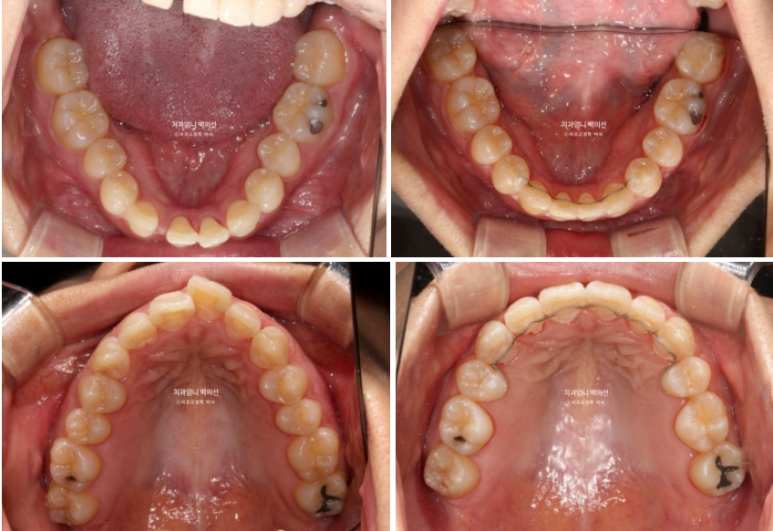

23.10~25.06

임플란트 없이 교정만으로 깔끔하게 마무리된 모습입니다.

양측 어금니 교합관계는 기존 3급에서 1급으로 개선되었고

앞니 덧니와 돌출이 해소가 되었습니다.